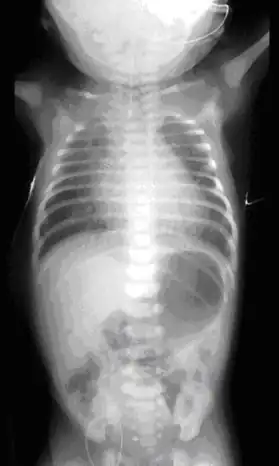

On plain X-ray, a feeding tube will not be seen pass through the esophagus and remain coiled in the upper oesophageal pouch.[8]

Plain X-ray of the chest and abdomen showing a feeding tube unable to move beyond an upper esophageal pouch. -

Plain x-ray with contrast in the upper esophagus above the atresia.